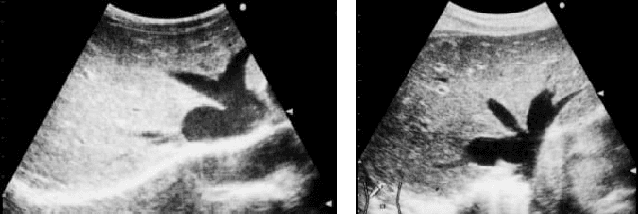

Abstract:Ring Theory states that a ring is an algebraic structure where two binary operations can be performed among the elements addition and multiplication. Binarization is a method of image processing where values within pixels are reduced to a scale from zero to one, with zero representing the most absence of light and one representing the most presence of light. Currently, sonograms are implemented in scanning for congestive heart failure. However, the renowned Playboy Bunny symbol representing the ailment becomes increasingly difficult to isolate due to surrounding organs and lower quality image productions. This paper examines the Otsu thresholding method and incorporates new elements to account for different image features meant to better isolate congestive heart failure indicators in ultrasound images.